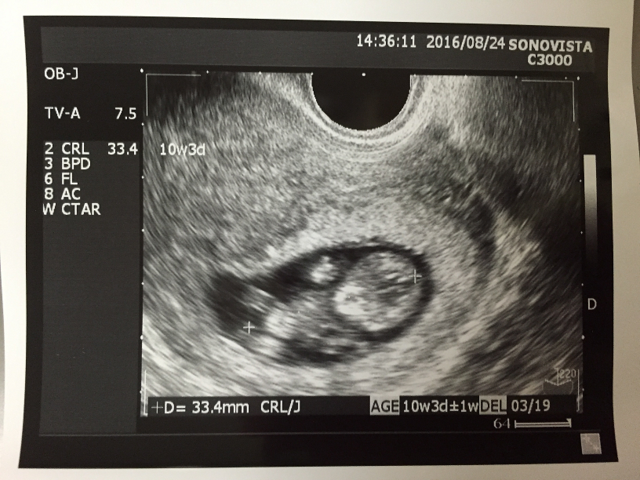

10週3日(10w3d・男の子)|りくえもん さん(32歳)

エコー写真撮影時のエピソード:

チョコレート嚢胞を患い、自然妊娠は難しいと言われ、体外受精を行なっていました。

昨年の秋に7週で稽留流産を経験し、今回上手くいかなかったら、嚢腫摘出手術をすると決めて挑んだ移植で、無事心拍確認ができました。

ただ、前回のこともあり、胎嚢確認ができても心拍確認ができてもまだまだ不安でしたが、このエコーで手足をもぞもぞさせて元気に動いている姿を確認し、やっと安心できました。